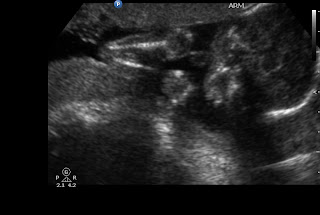

A baby boy to be specific! We found out yesterday at my 20 week appointment. He was sleeping for most of the ultrasound and wouldn't roll over, so I had to go back in 30 minutes later for a second so they could get photos from a few more angles. Who knew...

Here's a head and an arm.